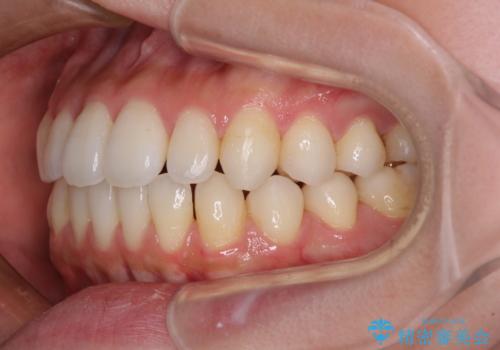

インビザラインで口を閉じやすく

- 下唇に上の前歯が当たることを気にして来院された患者様です。

上顎の親知らずを抜去し、歯列全体を後方に移動させるとともに、IPR(歯と歯の間を削る)を行うことで口元の閉じにくさを改善していくこととしました。

咬合力が強く、マウスピースを介した咬み込みが顕著であったため、奥歯の咬みにくさやIPRのスペースが改善しにくく、治療期間が思った以上にかかってしまいました。